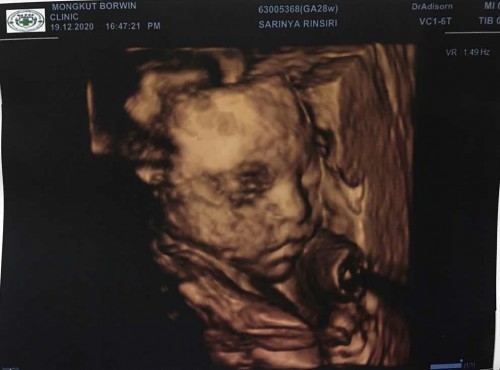

หนุ่มน้อย 28w เเล้วครับบ

รอบก่อนมือบังหน้า รอบนี้ดีหน่อยให้ได้เห็น

จมูก ปาก จิ้มลิ้ม 🥰